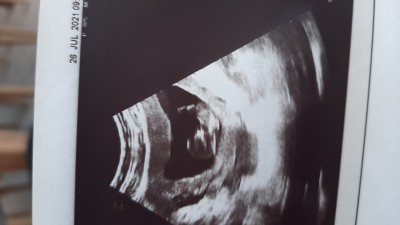

Kızlar merhaba ilk gebeliğim ancak cinsiyetini öğrenemedim var mı tahmininiz

Gebelik haftası 17+2